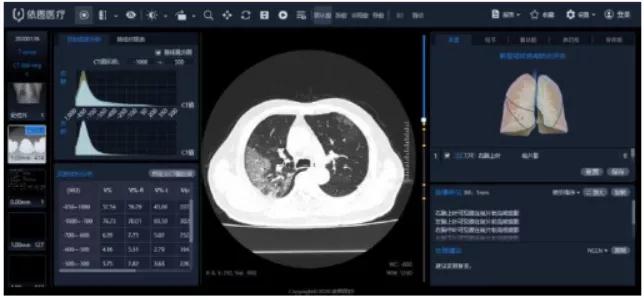

“看”-AI看片,輔助醫生診斷看片。當前醫學影像處理中,肺結節檢測等L域已經十分成熟,也是AI企業重要研究方向之一。得益于前期的積累,相關算法能夠快速遷移應用于新G肺炎疫情中。但是問題也很顯然,各個醫院的數據無法打通,且缺少有效標注數據;肺部影像輔助診斷發揮的實際效用有限,無法指導治療環節。

肺部影像分析系統